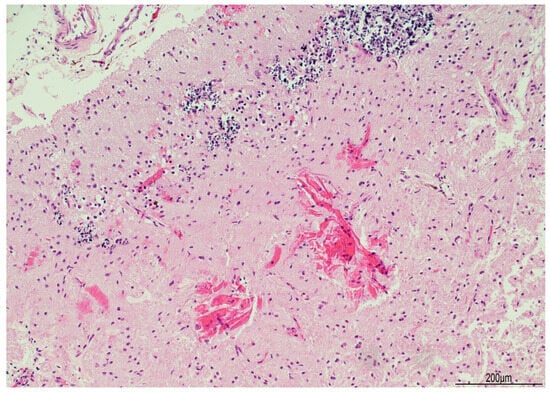

Tissue samples were formalin-fixed, paraffin-embedded, and stained with hematoxylin–eosin. Brain samples were very soft and most of the sections were disrupted after tissue processing. The brainstem showed neuronal ischemic changes, while the cerebellum showed ischemic features with Purkinje cell loss. The brain documented diffuse cortical and subcortical leukomalacia with neuronal loss, isomorphic and anisomorphic gliosis with reactive astrocytes and gemistocytes, Rosenthal fibers, and ferruginated residual neurons (Figure 4 and Figure 5). The meningeal arteries presented sub-adventitial mineralization of the tunica media and calcification of the external elastic lamina (Figure 6). Scattered microcalcifications were also found in the cerebral parenchyma as well as mineralization of the small and medium vessels. Special stains were not carried out as the histological findings were sufficiently informative for interpretation.

Figure 6. Calcification of the external elastic lamina of the meningeal arteries (Hematoxylin and Eosin, 10 HPF).